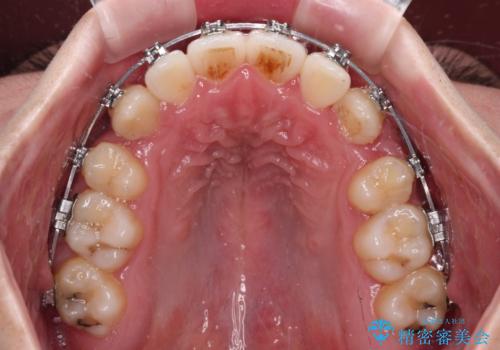

上下の八重歯とクロスバイト ワイヤー装置での抜歯矯正

- 八重歯とクロスバイトを気にして来院された患者様です。

上下ともに八重歯が顕著であり、前歯のクロスバイトがあったため、上下左右の第一小臼歯4本を抜歯し、ワイヤー装置での抜歯矯正を行うこととしました。